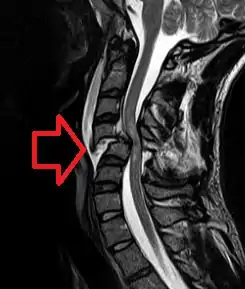

X-rays (left) are more available, but can miss details like herniated disks that MRIs can show (right).[60]

A radiographic evaluation using an X-ray, CT scan, or MRI can determine if there is damage to the spinal column and where it is located.[15] X-rays are commonly available[60] and can detect instability or misalignment of the spinal column, but do not give very detailed images and can miss injuries to the spinal cord or displacement of ligaments or disks that do not have accompanying spinal column damage.[15] Thus when X-ray findings are normal but SCI is still suspected due to pain or SCI symptoms, CT or MRI scans are used.[60] CT gives greater detail than X-rays, but exposes the patient to more radiation,[62] and it still does not give images of the spinal cord or ligaments; MRI shows body structures in the greatest detail.[15] Thus it is the standard for anyone who has neurological deficits found in SCI or is thought to have an unstable spinal column injury.[63]